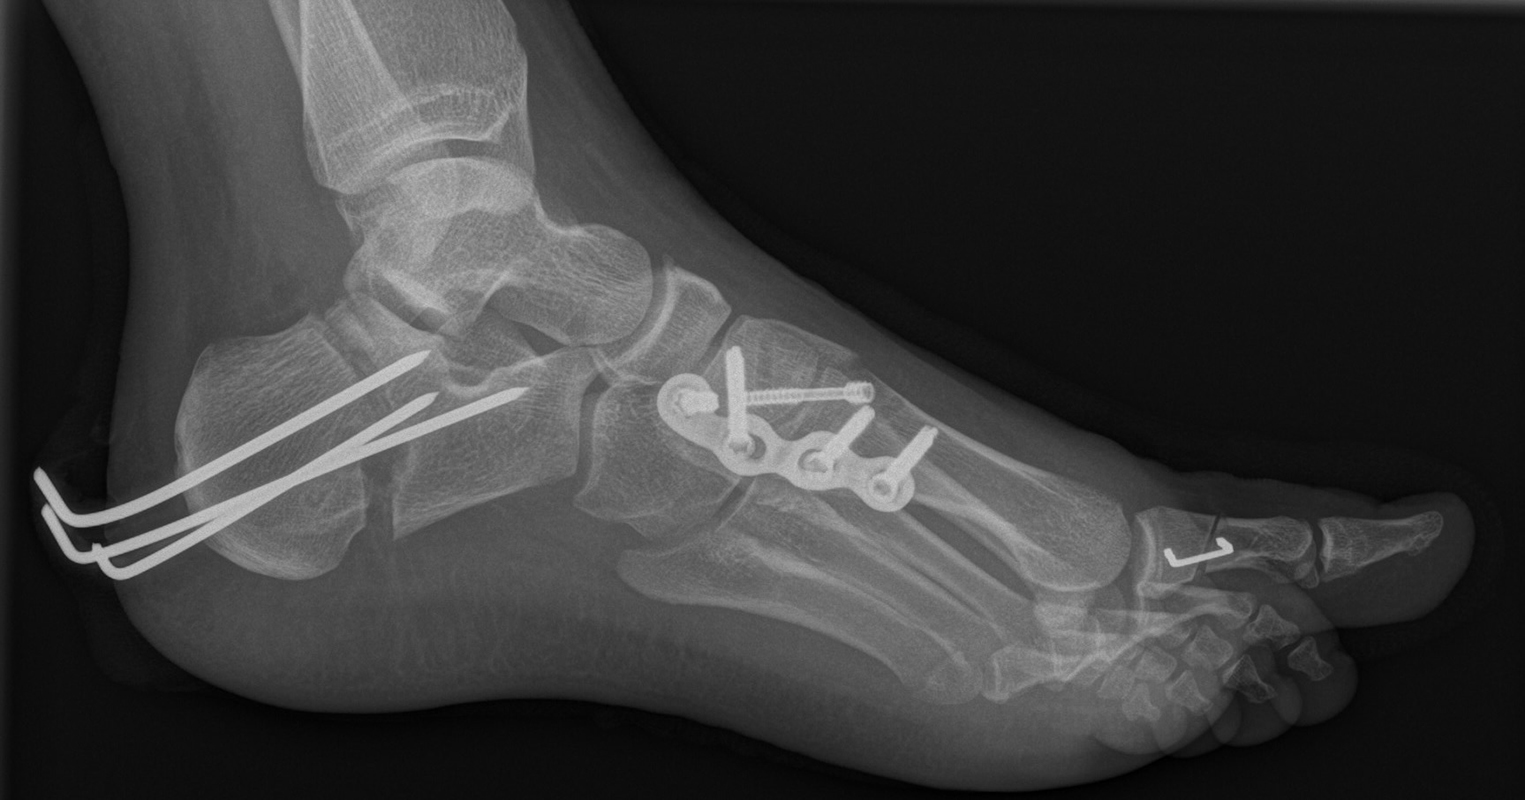

Knick-Senk-Platt-Fuß Korrektur mit dem Canalis Tarsi Spacer

In der Korrektur des schmerzhaften, aber flexiblen Knick-Senk-Fußes oder Plattfußes ist die Schraubenarthrorise mit einem Sinus tarsi oder besser bezeichnet als Canalis tarsi Spacer und alternativ mit einer Calcaneus-Stopp-Schraube seit vielen Jahren ein etabliertes Verfahren und führt zu einer kompletten Korrektur von flexiblen Knick- und Plattfuß-Fehlstellungen (Abb. 7). Die nötige Schnittlänge über dem Sinus tarsi beträgt für beide Verfahren 1 cm.

Calcaneus-Osteotomie

Die minimalinvasive Calcaneusverschiebeosteotomie bietet eindeutige Vorteile gegenüber dem offenen Verfahren, sodass wir bei Kindern und Jugendlichen nahezu keine offene Verschiebeosteotomie mehr durchführen. Am Calcaneus liegt die offene Wachstumsfuge dorsal. Bei der Durchführung müssen Schenkel der V-förmigen Osteotomie daher etwas steiler angelegt werden, in einem stumpfen Winkel (siehe Abb. 3 a-j). Für die Osteotomie liegen unsere Patienten auf dem Rücken und der BV wird für die exakte Seitaufnahme eingestellt. Der Fuß lagert auf einem hohen OP-Kissen und die Osteotomie kann bequem mit einem langen Kirschner-Draht und einem sterilen Stift angezeichnet werden (Abb. 15).

Damit lässt sich im Verlauf Röntgenstrahlung für die jungen Patienten vermeiden und die minimalinvasive Osteotomie kann sicher durchgeführt werden. Anschließend erfolgt die Verschiebung oder Impaktion. Ist ein Gleiten nach plantar oder cranial des distalen Fragmentes erwünscht, wird die Osteotomie schräg ohne V-Form entweder verlängernd oder verkürzend durchgeführt (Abb. 16).

Durch den knöchernen Defekt der Fräse gelingt die Verschiebung bei der minimalinvasiven Osteotomie im Fall von strukturell festen Klumpfüßen mit starkem Zug der verkürzten Achillessehne oder bei einer fixierenden spastischen Grunderkrankung einfacher gegenüber dem offen Verfahren. Ein weiteres Plus bei hyperaktiven Weichteilen ist die Vermeidung der ungewollten Cranialisierung des dorsalen Fragmentes durch die V-förmige Osteotomie (Abb. 16).

Die minimalinvasive Calcaneusverschiebeosoteotomie kommt somit in der Versorgung von kindlichen und jugendlichen Fußdeformitäten in einem weiten Erkrankungsspektrum zum Einsatz (Abb. 16):

- Plattfuß – Varisation

- Klumpfuß residual – Valgisation und ggfs. Cranialisation sowie Impaktion

- Klumpfuß überkorrigiert – Varisation und ggfs. Plantarisierung

- Hohlfuß – Cranialisation und ggf. Valgisation (alternativ minimalinvasive Austin-Osteotomie)

Abb. 16 a-f: Varisation einer valgischen Calcaneusstellung bei Knick-Senk-Fuß mit V-förmiger Osteotomie axiale Ansicht (a), seitliche Ansicht (b), d. p. Ansicht (c) und nach Entfernung der Drähte seitliche Ansicht (d), Caudalisierung des dorsalen Calcaneus bei iatrogenem Plattfuß nach Klumpfußüberkorrektur (e) und Cranialisierung beim Hohlfuß (f).